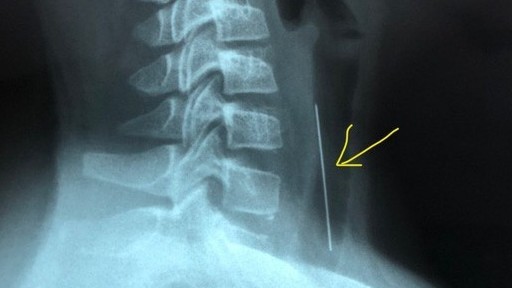

Tại bệnh viện địa phương, bé được Bác sĩ khám, chụp X-quang nghi ngờ có dị vật ở khí quản nên được chuyển đến Bệnh viện Nhi đồng 1 (TP. Hồ Chí Minh) với chẩn đoán theo dõi dị vật đường thở.

Ngay sau khi tiếp nhận, các bác sĩ đã nhanh chóng nội soi đường thở để gắp dị vật. Nhận định ban đầu của phẫu thuật viên khi nội soi: dị vật là 1 cây kim có 1 đầu nhựa quay xuống dưới, đầu nhọn quay lên trên và đâm vào thành khí quản khoảng 1cm chiều dài, kim nằm ở khí quản cách cựa khí quản khoảng 4-5cm.

Để gắp dị vật, các bác sĩ đã nắm đuôi kim đẩy kim xuống dưới để đưa đầu nhọn phía trên ra khỏi niêm mạc khí quản, rồi dùng kềm vi phẫu nắm đầu nhọn của kim đưa ra khỏi đường thở. Dị vật là 1 cây kim dài hơn 4cm với 1 đầu nhựa màu cam.